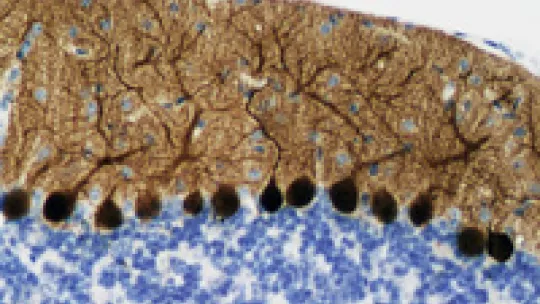

Collaborative research by groups headed by scientists Joan J. Guinovart and Marco Milán at the Institute for Research in Biomedicine (IRB Barcelona) has revealed conclusive evidence about the harmful effects of the accumulation of glucose chains (glycogen) in fly and mouse neurons. These two animal models will allow scientists to address the genes involved in this harmful process and to find pharmacological solutions that allow disintegration of the accumulations or limitation of glycogen production. Advances in this direction would make a significant contribution to investigation into Lafora progressive myoclonic epilepsy and other neurodegenerative diseases characterized by glycogen accumulation in neurons. The journal EMBO Molecular Medicine publishes the results of the study this week.

“Our data clearly indicate that glycogen accumulation alone kills neurons and thus dramatically reduces lifespan”, explains Guinovart, an expert in glycogen metabolism, group leader at IRB Barcelona, and senior professor at the University of Barcelona, “because the only thing we have manipulated in the neurons is their capacity to produce glycogen”.

The inclusion of the Drosophila fly in the study provides in vivo confirmation of the theory in another animal model as these flies also show the same symptoms of degeneration as mice when glycogen accumulates in neurons. However, in addition the use of Drosophila will speed up obtaining genetic data and the screening of therapeutic molecules. “In a short time we will be able to perform a massive search for genes involved in the pathological process and to understand it better at the molecular level”, emphasizes Marco Milán, ICREA researcher at IRB Barcelona and a specialist in Drosophila. “But the flies will also be useful to identify pharmacological molecules that can cure”, he explains.

The IRB Barcelona teams are designing several experiments to identify the possible therapeutic targets that may be useful to prevent glycogen accumulation in neurons. In addition to the direct relation to Lafora epilepsy, a progressive degenerative disease that affects adolescents and has no cure, glycogen accumulation could be the main cause of other neurodegenerative illnesses such as Adult polyglucosan body disease and Andersen’s disease.